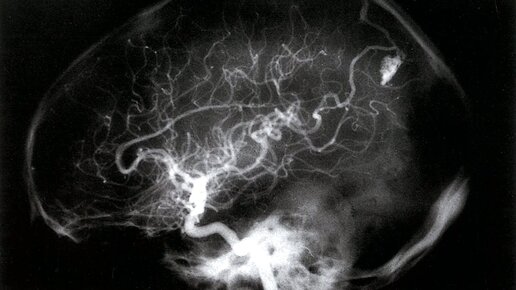

Что такое артериовенозные мальформации?

Артериовенозные мальформации, или "АВМ", представляют собой скопления аномальных кровеносных сосудов. У людей АВМ могут находиться в разных местах тела. Эта статья посвящена АВМ в головном мозге. АВМ в головном мозге являются редкостью и обычно формируются до рождения человека. Часто они не вызывают никаких симптомов, но иногда могут привести к серьезным симптомам или проблемам. Это может произойти, если АВМ оказывает давление на мозг или мешает достаточному снабжению его кислородом. Иногда АВМ также может разорваться и вызвать кровоизлияние в мозг...